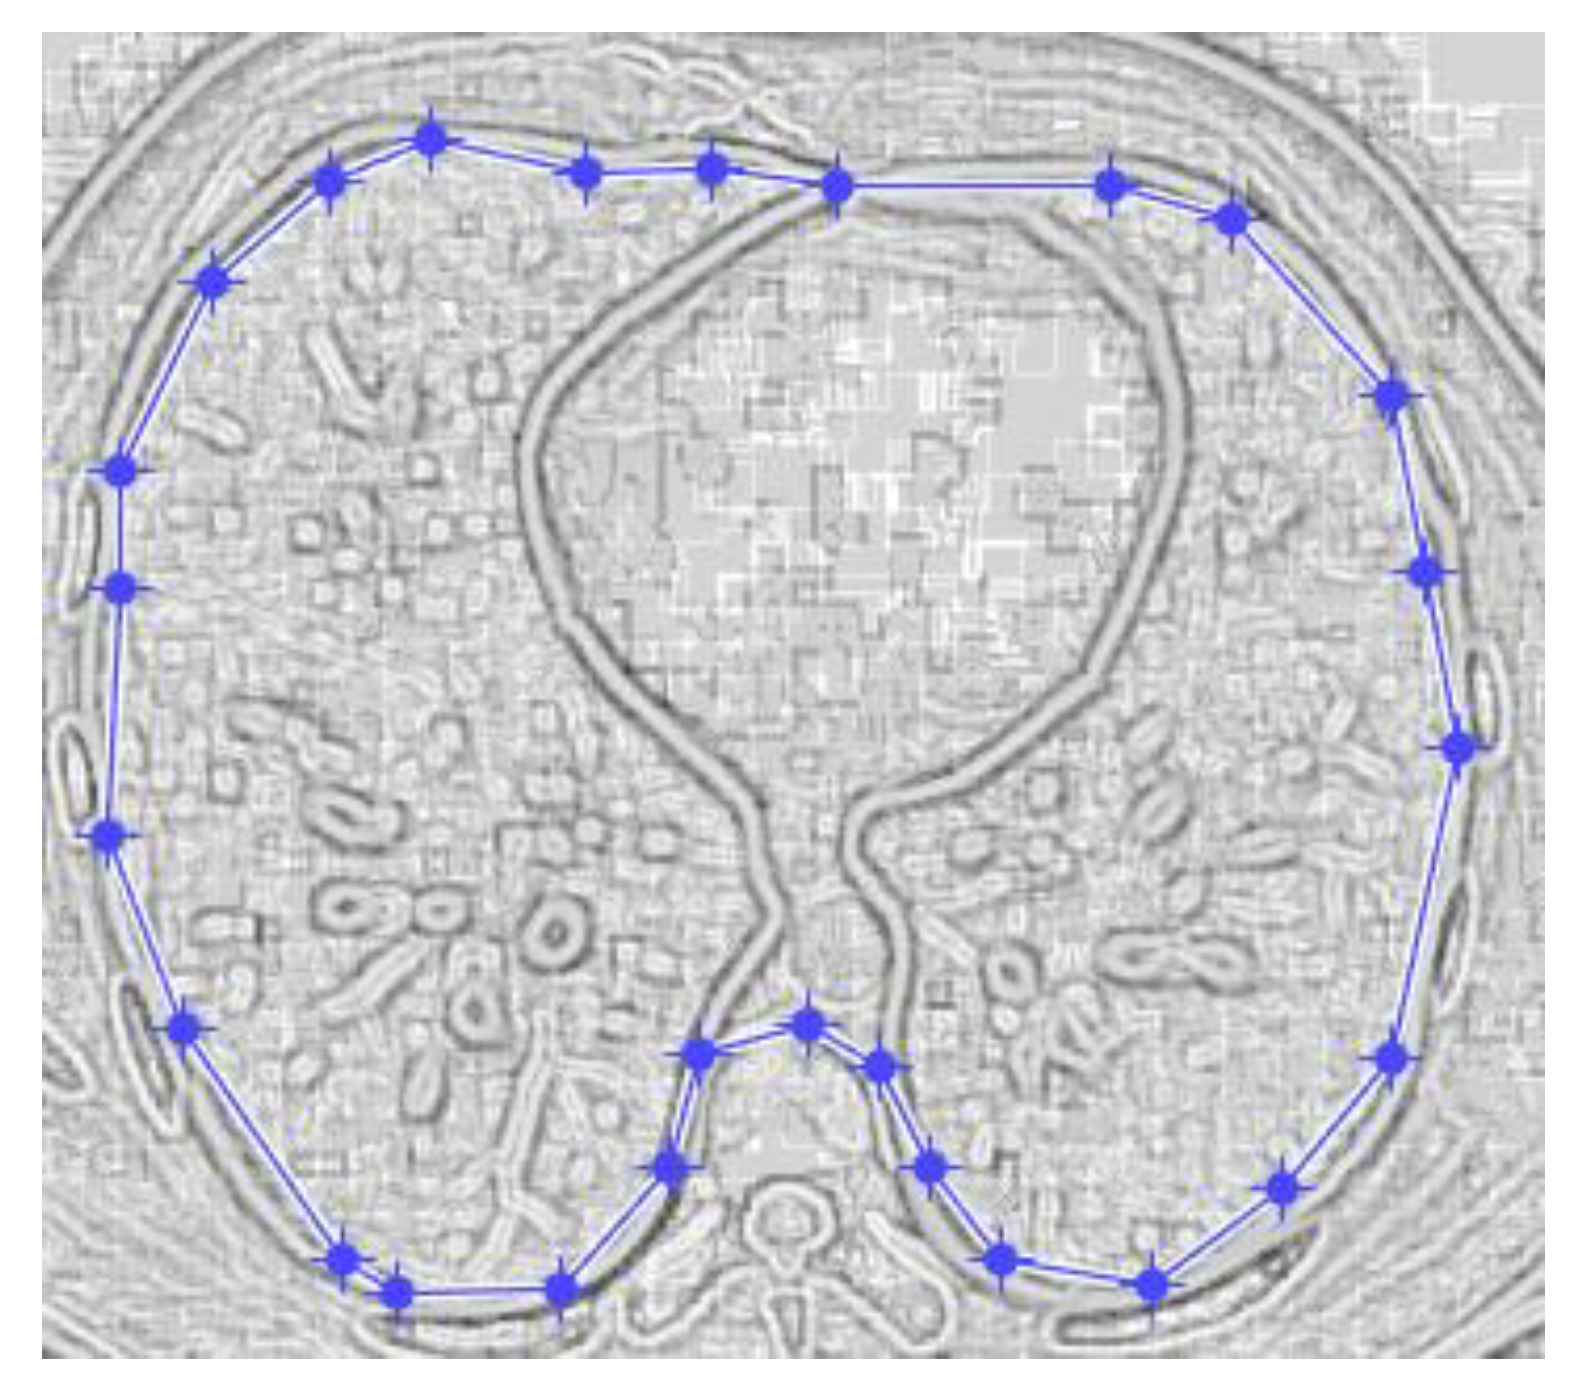

Figure 17 and Figure 18 show the original non-COVID-19 CT pulmonary picture, respectively, and the defined mask for the non-COVID-19 CT pulmonary picture, framed in a blue border, Figure 18.

Figure 18 presents the applied mask across the non-COVID-19 CT lung image, framed in a blue colour border.